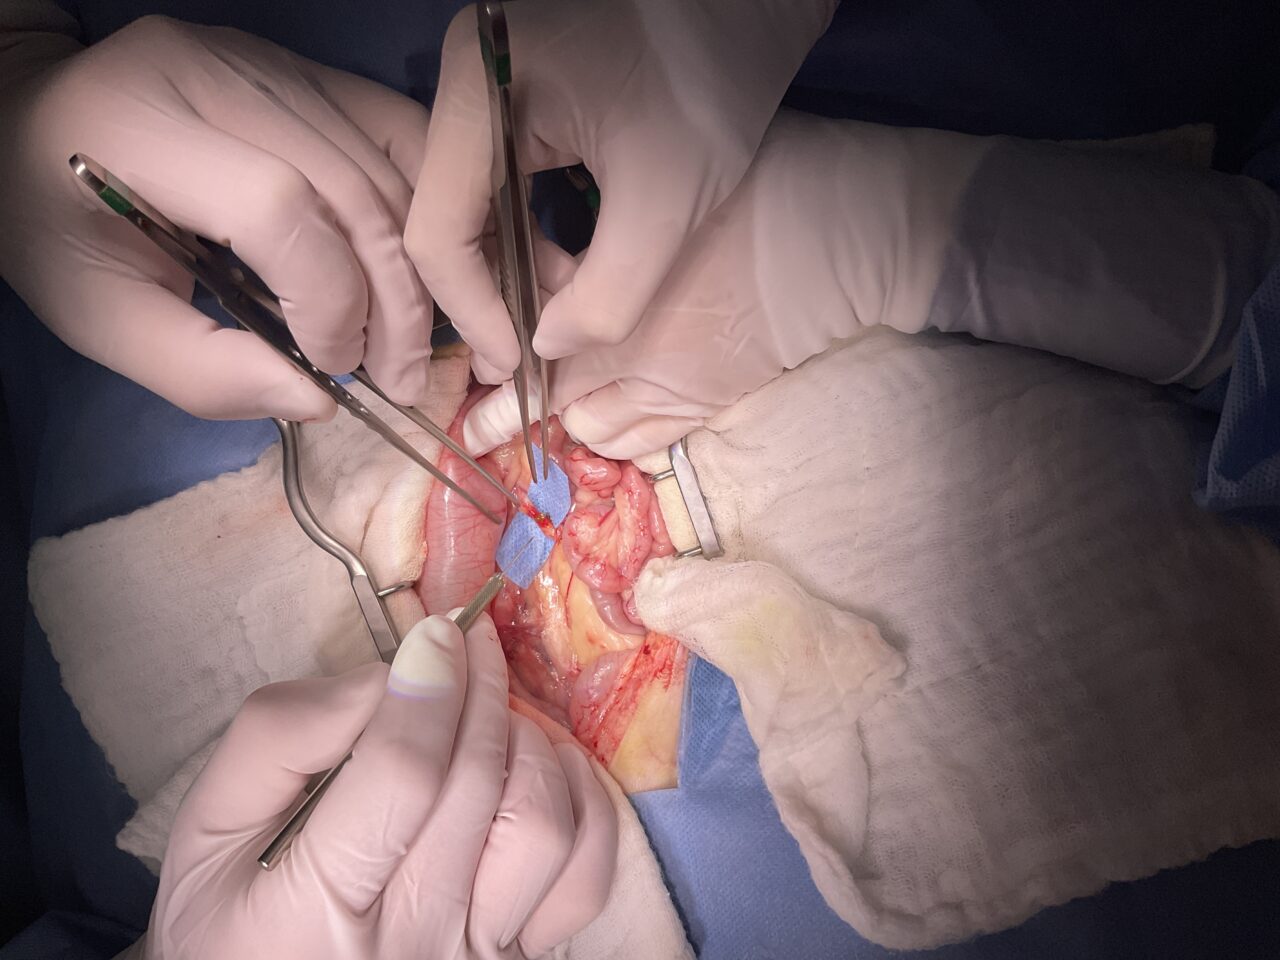

高齢の猫さんがかかりつけで慢性腎機能障害の治療中に急に腎数値が上昇したとのこと。精査を希望されて来院しました。CTで精査を行うと両側の尿管結石が確認され、顕微鏡下で両側の結石を摘除しました。術後数日は腎数値が改善しませんでしたが10日目頃より徐々に数値の改善とともに元気も出てきました。高齢ながら頑張ってくれました。